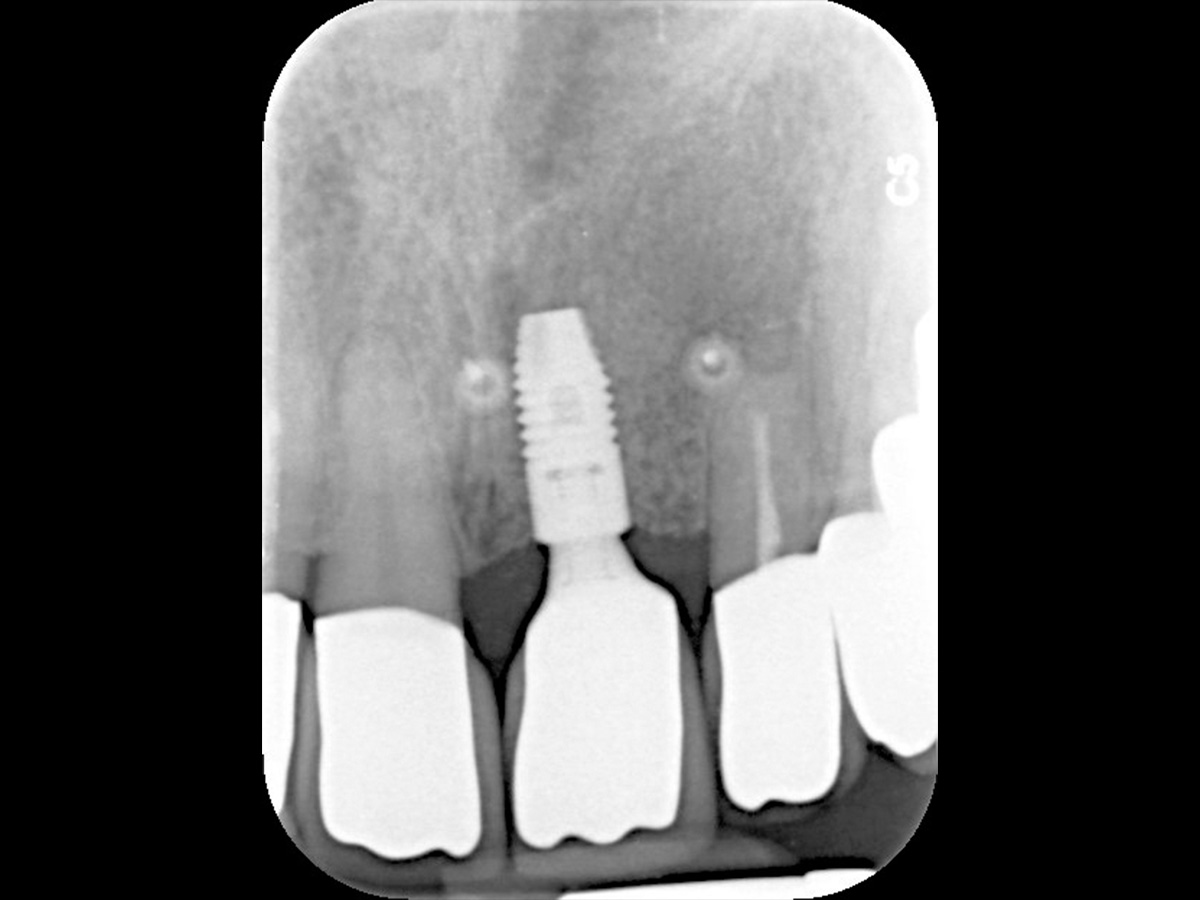

Abbildung 16

Röntgenkontrolle 2 Jahre nach Implantation.